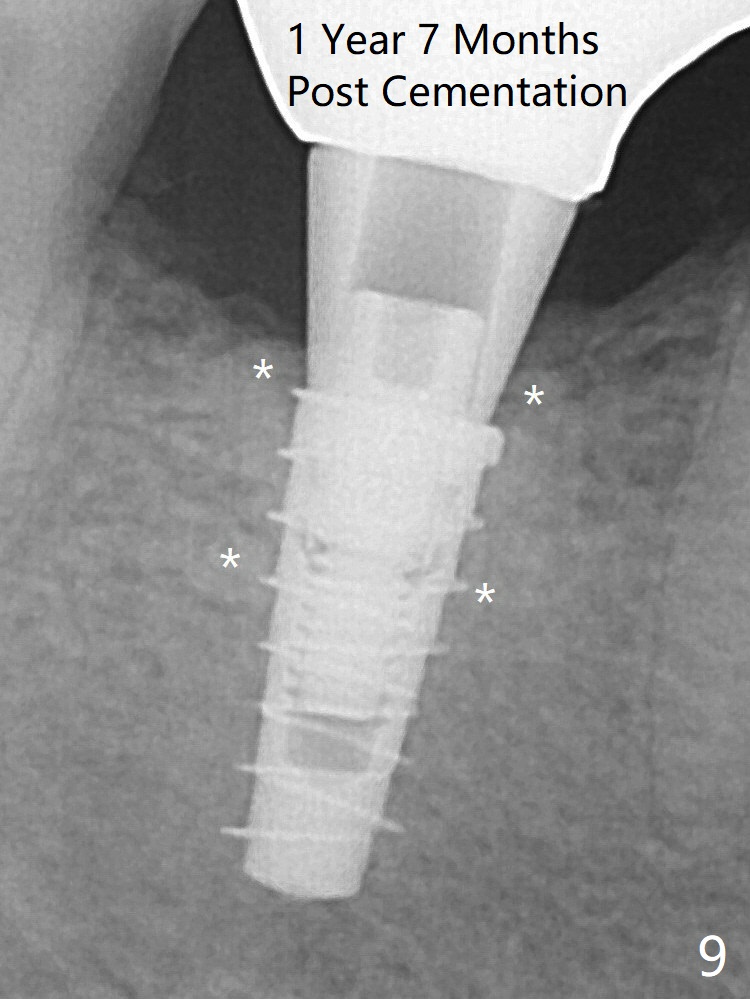

For safety, a 4x9 mm IBS implant is placed with insertion torque 40 Ncm; a 5x5.7(4) mm abutment is immediately placed for an immediate provisional to cover the large socket and keep Vera graft in place (Fig.4 *). Yellow dashed line: apical osteotomy; red dashed line: Mental Loop. Impression is taken nearly 3 months postop (Fig.6). The bone density around the implant increases 7 months post cementation (Fig.8 *). The higher density bone seems to extend coronally 1 year 7 months post cementation (Fig.9).